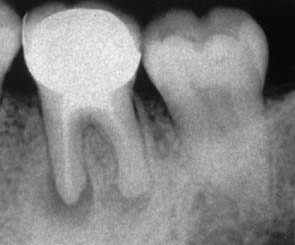

Patients often forget which teeth have been endodontically treated. These can be readily identified with radiographs. The findings should be reviewed periodically so that periapical health can be monitored and any recurring lesions promptly detected (Fig. 1-6).

Occlusal analysis should be an integral part of the assessment of a postorthodontic dentition. If restorative treatment needs are anticipated, they should be undertaken by the restorative dentist. Occlusal adjustment (reshaping of the occlusal surfaces of the teeth) may be needed to promote long-term positional stability of the teeth and reduce or eliminate parafunctional activity. On occasion, root resorption (detected on radiographs) (Fig. 1-7) may be attributable to previous orthodontic treatment. As the crown/root ratio is affected, future prosthodontic treatment and its prognosis may also be affected. Restorative treatment can often be simplified by minor tooth movement. When a patient is contemplating orthodontic treatment, considerable time can be saved if minor tooth movement (for restorative reasons) is incorporated from the start. Thus, good communication between the restorative dentist and the orthodontist may prove very helpful.